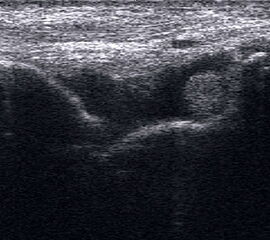

Fibulaverletzung beim Kind

Abgehobenes Periost mit periostalem Hämatom (rechts) mit Gegenseite (links). Die Kortikalis wird unterbrochen von der noch offenen Wachstumsfuge der Fibula.

Abbildung 12

Lagerung: Rückenlage, leichte Innrotation des Fußes.

Schnittebene: LS über distaler Fibula.

Referenzstruktur: Fibula im Längsverlauf.

Befunde: Bei Kindern wird nach Distorsion des OSG mitunter eine Lösung der Fibulafuge vermutet, die jedoch in der klinischen Praxis sehr selten ist. Die seitenvergleichende Untersuchung zeigt dann ein aufgrund des dicken und bei Kindern gut abgrenzbaren echogenen Periosts ein periostales Hämatom, was aber auch ein Hinweis auf eine Fissur oder Fraktur sein kann (Abb.12).